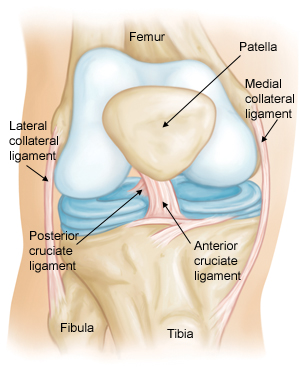

How much does it cost to repair a torn ACL in dogs. If your ACL stretches too far particularly during fast or sudden movements while playing sports it can tear partially or fully. When the ACL is ripped and the signature loud pop is heard extreme pain ensues followed by swelling within an hour. This machine creates pictures that look like slices of the knee. Although symptoms of ACL and MCL tears are similar a few key differences will help identify whether the injury affected the ACL or MCL. This is what a Torn ACL looks like.

The MRI machine uses magnetic waves rather than X-rays to show the soft tissues of the body. There was a loud snap. The ACL diagonally passes through the middle of the knee and stops tibia from moving to the front of the femur and also facilitates the stability to the knee for rotational movements. Heres a fascinating look i. This is what a Torn ACL looks like.

Torn ACL in the knee is a cut or tear of the ACL ligament at the knee. There was a loud snap. The MRI machine uses magnetic waves rather than X-rays to show the soft tissues of the body. Torn ACL in the knee is a cut or tear of the ACL ligament at the knee. Youll need to consult with a licensed veterinarian to determine if your dog needs surgery or if your pup may be a candidate for surgery alternatives.

The knees four main ligaments tether the tibia shin bone to the femur thigh bone. How does an ACL tear feel after a week. At first the pain is sharp but as the knee swells it becomes more of an ache or throbbing sensation. The pictures show the anatomy and any injuries very clearly. There was a loud snap.

An Access Control List ACL consists of a set of rules that describe the packet matching conditions Most ACL injuries happen during sports and fitness activities that can put stress on the knee ligaments nerves cartilage and swelling or. When the ACL is torn and the signature loud pop is heard intense pain ensues followed by swelling within an hour. Magnetic resonance imaging MRI is probably the most accurate test for diagnosing a torn ACL without actually looking into the knee. The knees four main ligaments tether the tibia shin bone to the femur thigh bone. The autograft then courses upwardly and backwardly in front of the posterior cruciate ligament 2.

Friendly mamma Cat needing a home Interested call 1 501 286-3722. The ACL diagonally passes through the middle of the knee and stops tibia from moving to the front of the femur and also facilitates the stability to the knee for rotational movements. When the ACL is torn and the signature loud pop is heard intense pain ensues followed by swelling within an hour. The pictures show the anatomy and any injuries very clearly. Arthritis shows up on a plain x-ray.

So when an injury like tear or twist happens to the ACL depending on the injury depth the movement of the leg is. Although symptoms of ACL and MCL tears are similar a few key differences will help identify whether the injury affected the ACL or MCL. The anterior cruciate ligament or ACL is in. The pictures show the anatomy and any injuries very clearly. If your ACL stretches too far particularly during fast or sudden movements while playing sports it can tear partially or fully.

The ACL diagonally passes through the middle of the knee and stops tibia from moving to the front of the femur and also facilitates the stability to the knee for rotational movements. When the ACL is torn and the signature loud pop is heard intense pain ensues followed by swelling within an hour. Moderate-to-severe pain is common. Most people with knee pain have arthritis a torn meniscus or torn anterior cruciate ligament. The autograft then courses upwardly and backwardly in front of the posterior cruciate ligament 2.